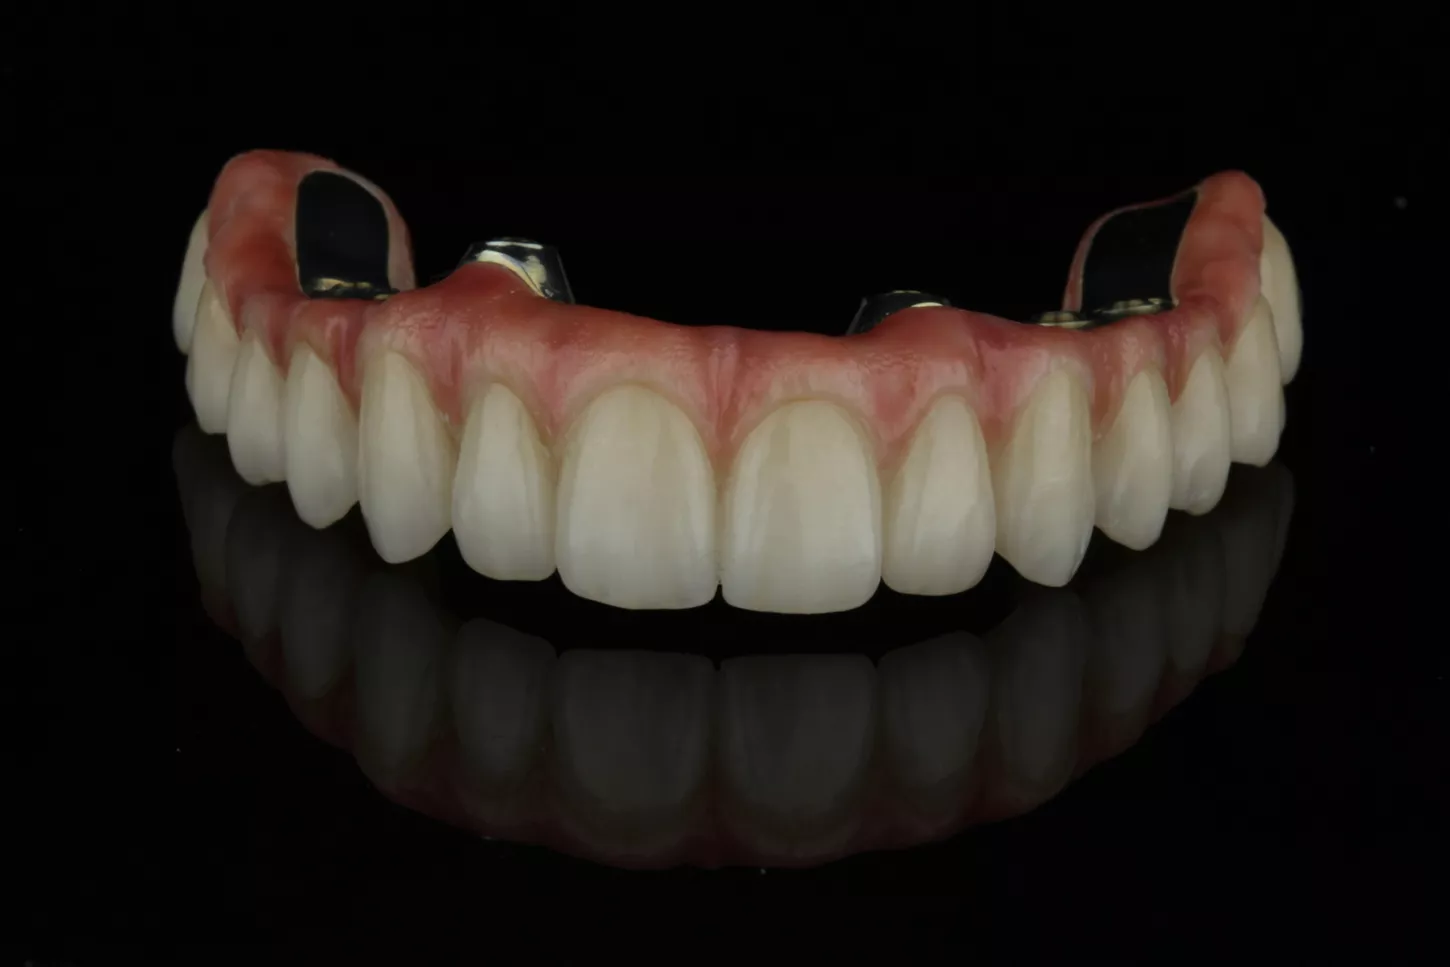

17. Once the designs of our restorations and the various relevant tests had been carried out, we received the prostheses. Both structures (the titanium and monolithic zirconia) were entirely milled in the Simeda® centre and designed by the Corus Garbident laboratory in Vitoria (Spain).

17

18a. 18b. Images of the upper restoration.

18a

18b

19a. 19b. Images of the lower restoration.

19a

19b

20a. 20b. In this clinical case, and as a novelty, we were able to screw both structures directly to the implants, since, the angled chimneys were incorporated in the titanium structure itself, in this case anodized to improve the final aesthetics.

20a

20b